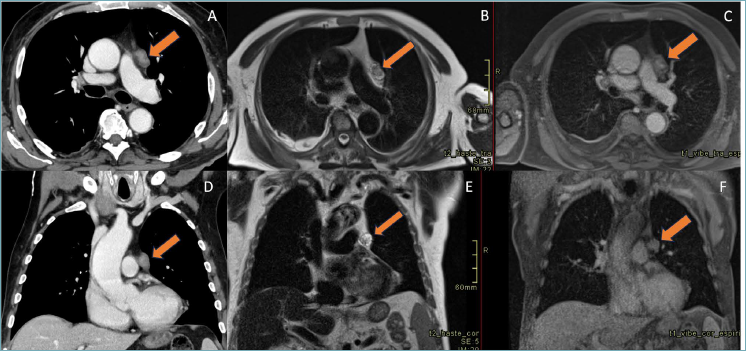

Computed tomography (CT) examination revealed a solitary, well-circumscribed, poorly-enhanced lesion in the anterior mediastinum, approximately 3x3x2 cm in size, raising suspicion of a thymic neoplasm and prompting further investigation via imaging (Fig. 1 A, D). Magnetic resonance imaging (MRI) confirmed a heterogenous, hypointense lesion (Fig. 1 B, E) and a homogeneous enhancement on post-contrast T1- weighted images (Fig. 1 C, F). No lymph node metastases or other localization of disease were detected.

Figure 1. A) Axial and D coronal post-contrast CT imaging revealed a poor enhancement of a small, rounded well-defined lesion; B) Axial and E coronal non-contrast- enhanced T2- weighted MRI scans showed hypointensity, within a heterogeneous anterior mediastinal lesion extending into thymic rest. C) Axial and F coronal post-contrast-enhanced T1- weighted MRI scans showed a homogeneously enhanced lesion.